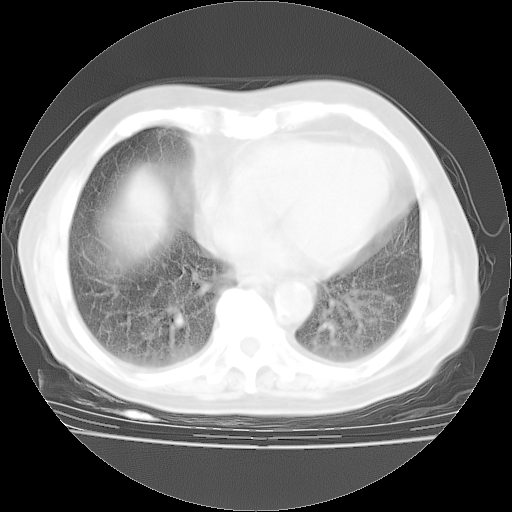

4月28日肺部CT——再次出现类似去年5月9日——透光度降低,“间质性”改变。

4月28日肺部CT——再次出现类似去年5月9日——磨玻璃样、间有“粟粒样”改变。

个人阅读4.14日肺部CT平扫:纵隔窗无异常,但肺窗示:双下肺内、后基底段有片絮状侵润影,部位以后基底段为著,以间质改变为主,呈急性肺泡炎征像,和首次住院影像学有相似之处。仅是个人读片,明日请相关专家再读片哈。其它建议同上。

1、108#的是4月14日的胸部CT(发此贴时还没看着28日的CT)。14日的胸部CT其实已经出现改变(如108#所述),个人认为28日的胸部CT除纵膈窗疑似有双侧胸膜增厚或少量胸积液(可行胸部B超明确)外,与4月14日对照病变有所加重;2、已经给予“异烟肼、利福平、乙胺丁醇”抗痨治疗?如果是,甲强龙80mg可缓慢减量;如果环磷酰胺已停用,暂不使用;3、中性粒细胞92%,明显升高,目前体温情况?注意合并细菌感染可能,使用左氧氟沙星情况下,是否联用B-内酰胺类抗菌药物?另外是查免疫全套非风湿全套。

今请临免主任会诊后认为:4月14日胸部CT已有双下肺间质性改变。患者病情复发多系激素减量过快不正规所致。目前甲强龙80mg/日,一周后酌情开始减量,不易过快。环磷酰胺若已停用,暂不使用。他同意目前抗菌药物使用,但应考虑是否加用B-内酰胺类抗菌药物(中性细胞明显增高);2、结核复发目前依据不足;3、若免疫全套各项指标正常,考虑多系特发性肺间质炎可能大。4、加强支持,并注意保护胃黏膜。

今上午去请教了临免、呼吸主任:1、介绍病史和阅读系列胸部CT一致认为:患者肺结核不考虑,仍为肺间质纤维化,目前处于急性肺泡炎阶段。2、若仍发热,可将甲强龙增至:80mg Bid静滴,同时鉴于中性增高,合并细菌感染可能,继续左氧氟沙星治疗,再联用B-内酰胺抗菌药物,如头孢哌酮--舒巴坦;3、停用抗痨药;4、目前甲强龙每日剂量160mg ,体温正常后再酌情减量;目前暂不用免疫抑制剂;4、不建议使用免疫增强剂等;5、加强支持治疗,鼓励患者进食;5、注意随访肝、肾功及血常规情况;6、因患者目前激素用量较大,加用胃黏膜保护剂,防止消化道出血可能。